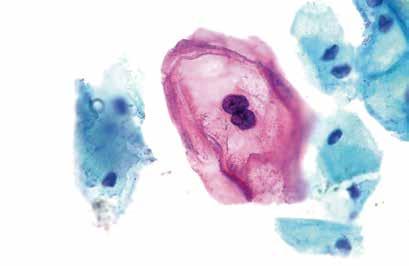

62 Vacina terapêutica testada em roedores eliminou tumores causados pelo vírus HPV